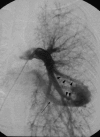

This pictorial review is based on our experience of the follow-up of 120 patients at our multidisciplinary center for hereditary hemorrhagic telangiectasia (HHT). Rendu-Osler-Weber disease or HHT is a multiorgan autosomal dominant disorder with high penetrance, characterized by epistaxis, mucocutaneous telangiectasis, and visceral arteriovenous malformations (AVMs). The research on gene mutations is fundamental and family screening by clinical examination, chest X-ray, research of pulmonary shunting, and abdominal color Doppler sonography is absolutely necessary. The angioarchitecture of pulmonary AVMs can be studied by unenhanced multidetector computed tomography; however, all other explorations of liver, digestive bowels, or brain require administration of contrast media. Magnetic resonance angiography is helpful for central nervous system screening, in particular for the spinal cord, but also for pulmonary, hepatic, and pelvic AVMs. Knowledge of the multiorgan involvement of HHT, mechanism of complications, and radiologic findings is fundamental for the correct management of these patients.